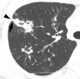

Pleuropulmonary fibrosis at lung apex